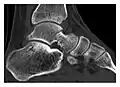

Figure 6: Subtle anterior talar fracture in a 39-year-old man presenting with ankle pain after a fall. (a) Anteroposterior radiograph shows a subtle oblique radiolucent line through the talus (white arrows). (b) Sagittal CT reformation confirms the presence of an anterior talar fracture with cortical offset (black arrow). Avulsion fractures, which consist of a detached bone fragment resulting from a ligament or tendon pulling away from the bone, may also present with subtle radiographic signs. Tiny osseous fragments near the presumed attachment site of a ligament suggest this diagnosis. Common sites are the lateral tibial plateau (the Segond fracture), the spinal tuberosity of the tibia resulting from anterior cruciate ligament avulsion, and the ischial tuberosity.[1]